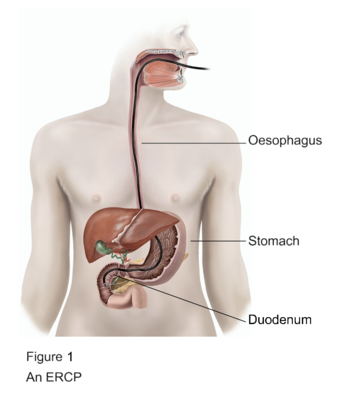

ERCP is a minimally invasive procedure. During this process, a thin flexible tube with a camera is passed through the mouth. It reaches the stomach and small intestine. This allows the doctor to see the bile duct clearly.

In addition, small tools can remove stones or open blocked ducts. Therefore, ERCP treatment in Bhopal helps both in diagnosis and treatment.